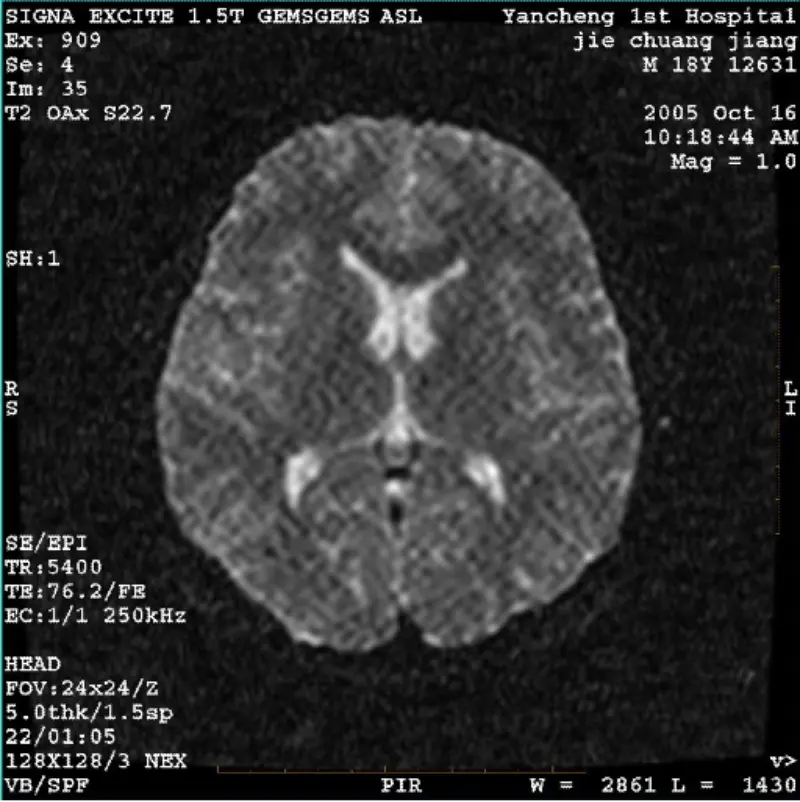

Leer másSISTEMA: 1.5T Signa Twin Excite II (Versión de software 11.0M4) PROBLEMA/SÍNTOMAS Imagen DWI (modo zoom y modo completo) y fiesta (modo zoom y modo completo) que tiene artefacto reticulado o de pana visible sin importar si se utiliza la bobina del cuerpo o la cabeza bobina, otra imagen de rut......